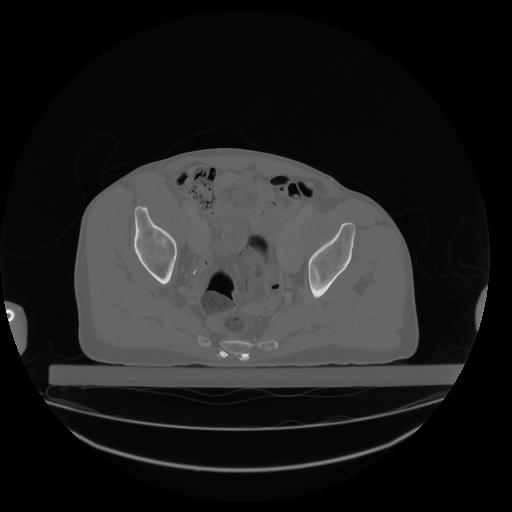

27 CUERPO,CE,Axial,3.0,CUERPO,,